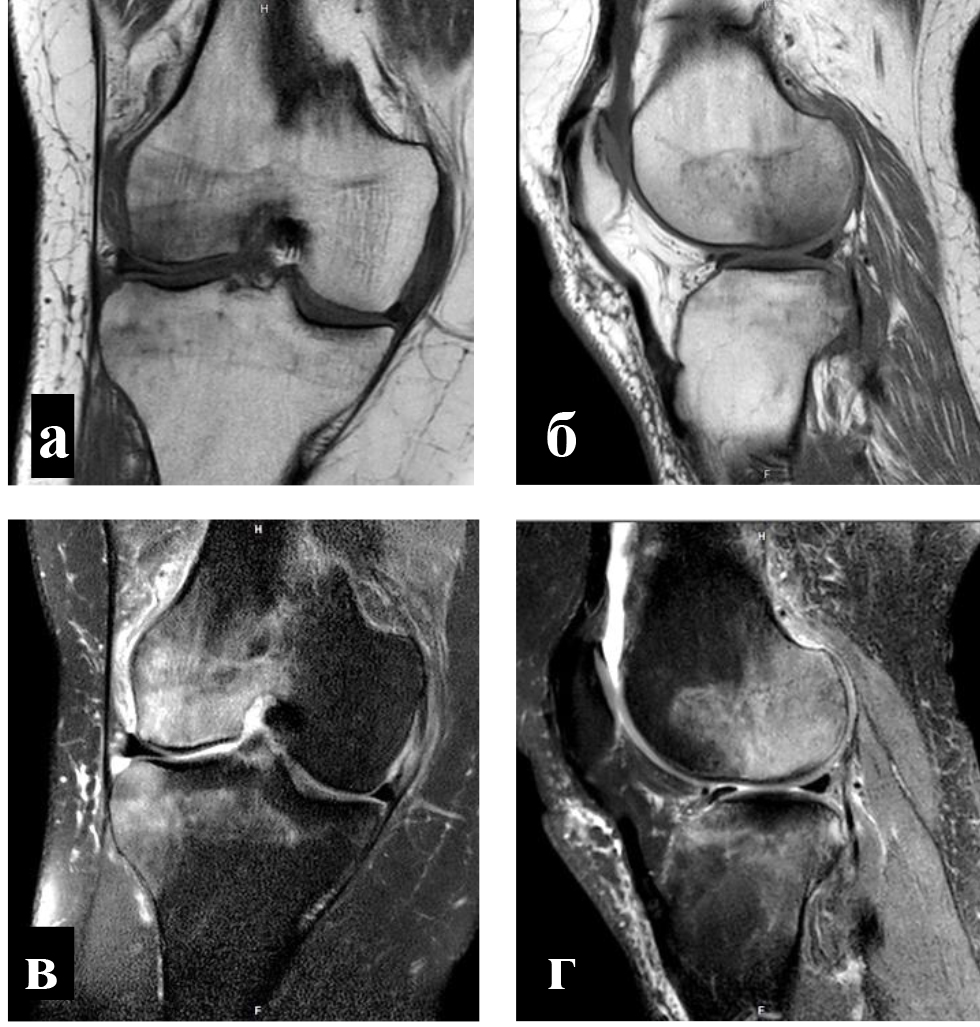

Для определения локализации и распространенности перегрузочного отека костного мозга всем пациентам выполняли МРТ. На Т1-взвешенных изображениях визуализировали снижение интенсивности сигнала, на Т2-взвешенных изображениях с жироподавлением и на коротких последовательностях «восстановления – инверсии» (STIR) выявляли высокую интенсивность сигнала (рис. 1).

Объективным показателем регресса болевого синдрома и нормализации клеточного метаболизма субхондральных структур являлось значительное сокращение объема или вовсе исчезновение зон трабекулярного отека костного мозга, что подтверждалось уменьшением гиперинтенсивных участков по данным МРТ (рис. 4) [8].